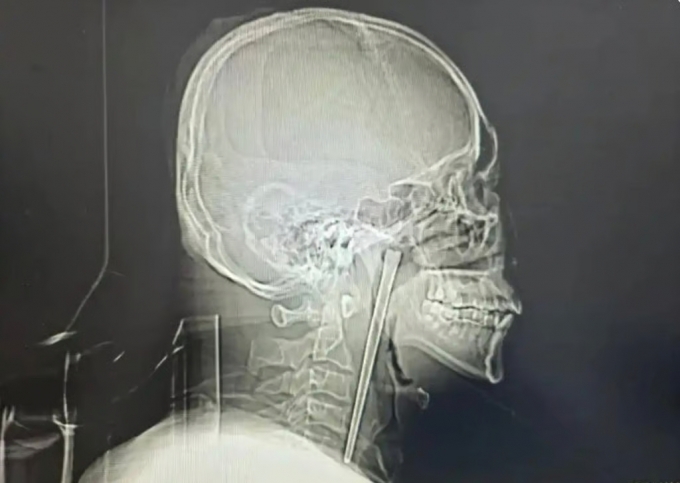

중국에서 길이 12㎝의 금속 젓가락이 목에 박힌 채 8년을 버티다 최근 제거 수술을 받은 남성의 사연이 알려졌다. /사진=사우스차이나모닝포스트 |

중국에서 길이 12㎝의 금속 젓가락이 목에 박힌 채 8년을 버티다 최근 제거 수술을 받은 남성의 사연이 알려졌다. /사진=바이두 |

정밀 검사 결과 왕씨가 삼킨 금속 젓가락은 목 안쪽 연구개 부위에 박혀 있었던 것으로 확인됐다. 의료진은 다행히 주변 점막에 손상이 없고 성대 기능 역시 정상적으로 유지되고 있었다고 설명했다. 그러면서 목 절개를 거부한 환자의 의사를 반영해 구강을 통한 최소침습 수술을 진행했고 12㎝ 길이의 젓가락을 성공적으로 제거했다.